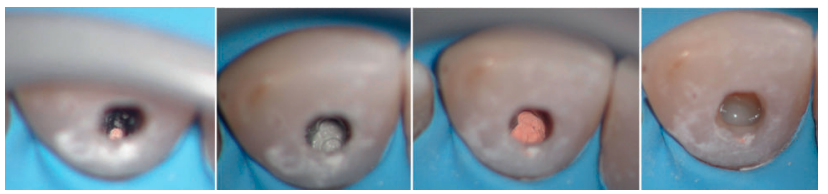

En la primera sesión, al realizar la apertura se detecta un tejido inflamatorio (Figura 3) procedente de la reabsorción interna, con lo que se procede a realizar irrigación con hipoclorito al 2,5 % (Dentaflux, Madrid, Spain) y colocación medicación intraconducto de hidróxido de calcio (Calcicur, Voco, Cuxhaven, Alemania) durante 7 días11 .

En una segunda sesión y con el conducto libre de tejido inflamatorio, se confirma la longitud de trabajo (22 mm) con una lima 10 K-file (Dentsply Maillefer, Ballaigues, Switzerland). Se instrumenta hasta X2 (25.06) de Protaper Next (Dentsply Maillefer, Ballaigues, Switzerland) y se realiza el protocolo de irrigación final: NaOCL 2,5% EDTA 17% NaOCL 2,5%. Ambos irrigantes fueron activados de manera hidrodinámica con la lima Xp-Finisher (Fkg Dentaire, La ChauxdeFonds, Switzerland) de diámetro 25 sin conicidad, a una velocidad 1000 rpm y torque de 1Nw. Se procede al secado intraconducto con puntas de papel del número 25 (Dentsply Maillefer, Ballaigues, Switzerland), donde se puede apreciar la diferencia entre el conducto y la perforación hacia vestibular (Figura 4). A continuación, se realiza una conometría con gutapercha calibrada tipo Autofit del 6% (Kavo-Kerr, California, Estados Unidos), comprobando la existencia de un correcto stop apical.